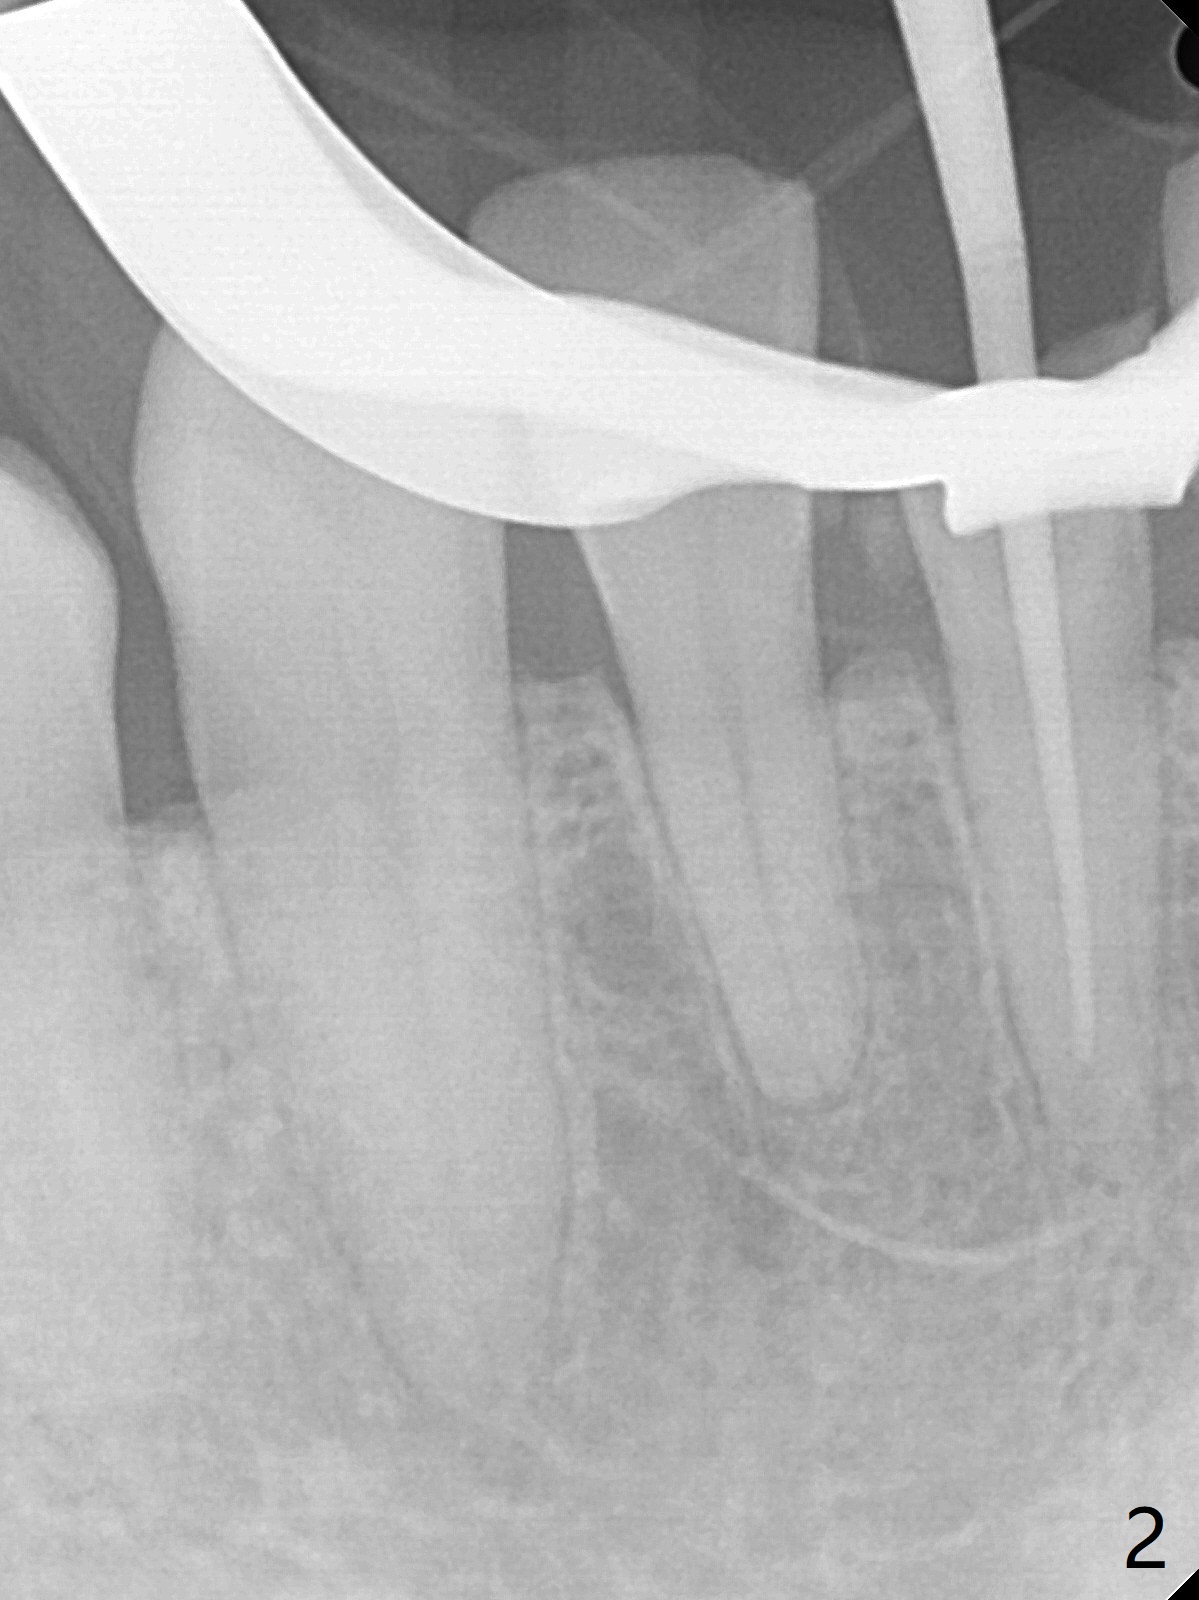

A 31-year-old woman fractured the lower left central incisor when it was hit by her 2-year-old son's head with mesiobuccal subgingival margin (Fig.1). After RCT (Fig.2), gingivectomy is conducted with eletrosurg to expose the fractured margin (Fig.3). In 2 days, a prefabricated fiber post will be bonded with the tooth and the fractured fragment together. To extend the use of the incisor, two implants are required (Fig.4). As scheduled, the patient returns with the fractured portion (Fig.5,6 (buccal (B) and lingual (L) views)). The periodontal dressing is in place (Fig.7 P). After preparation of the post space, the fiber post (Fig.10 (P)) is bonded with resin cement (Fig. 10 ^ and *) to the tooth and fragment with rubber dam (Fig.8). The patient is pleased post occlusal adjustment (Fig.9).